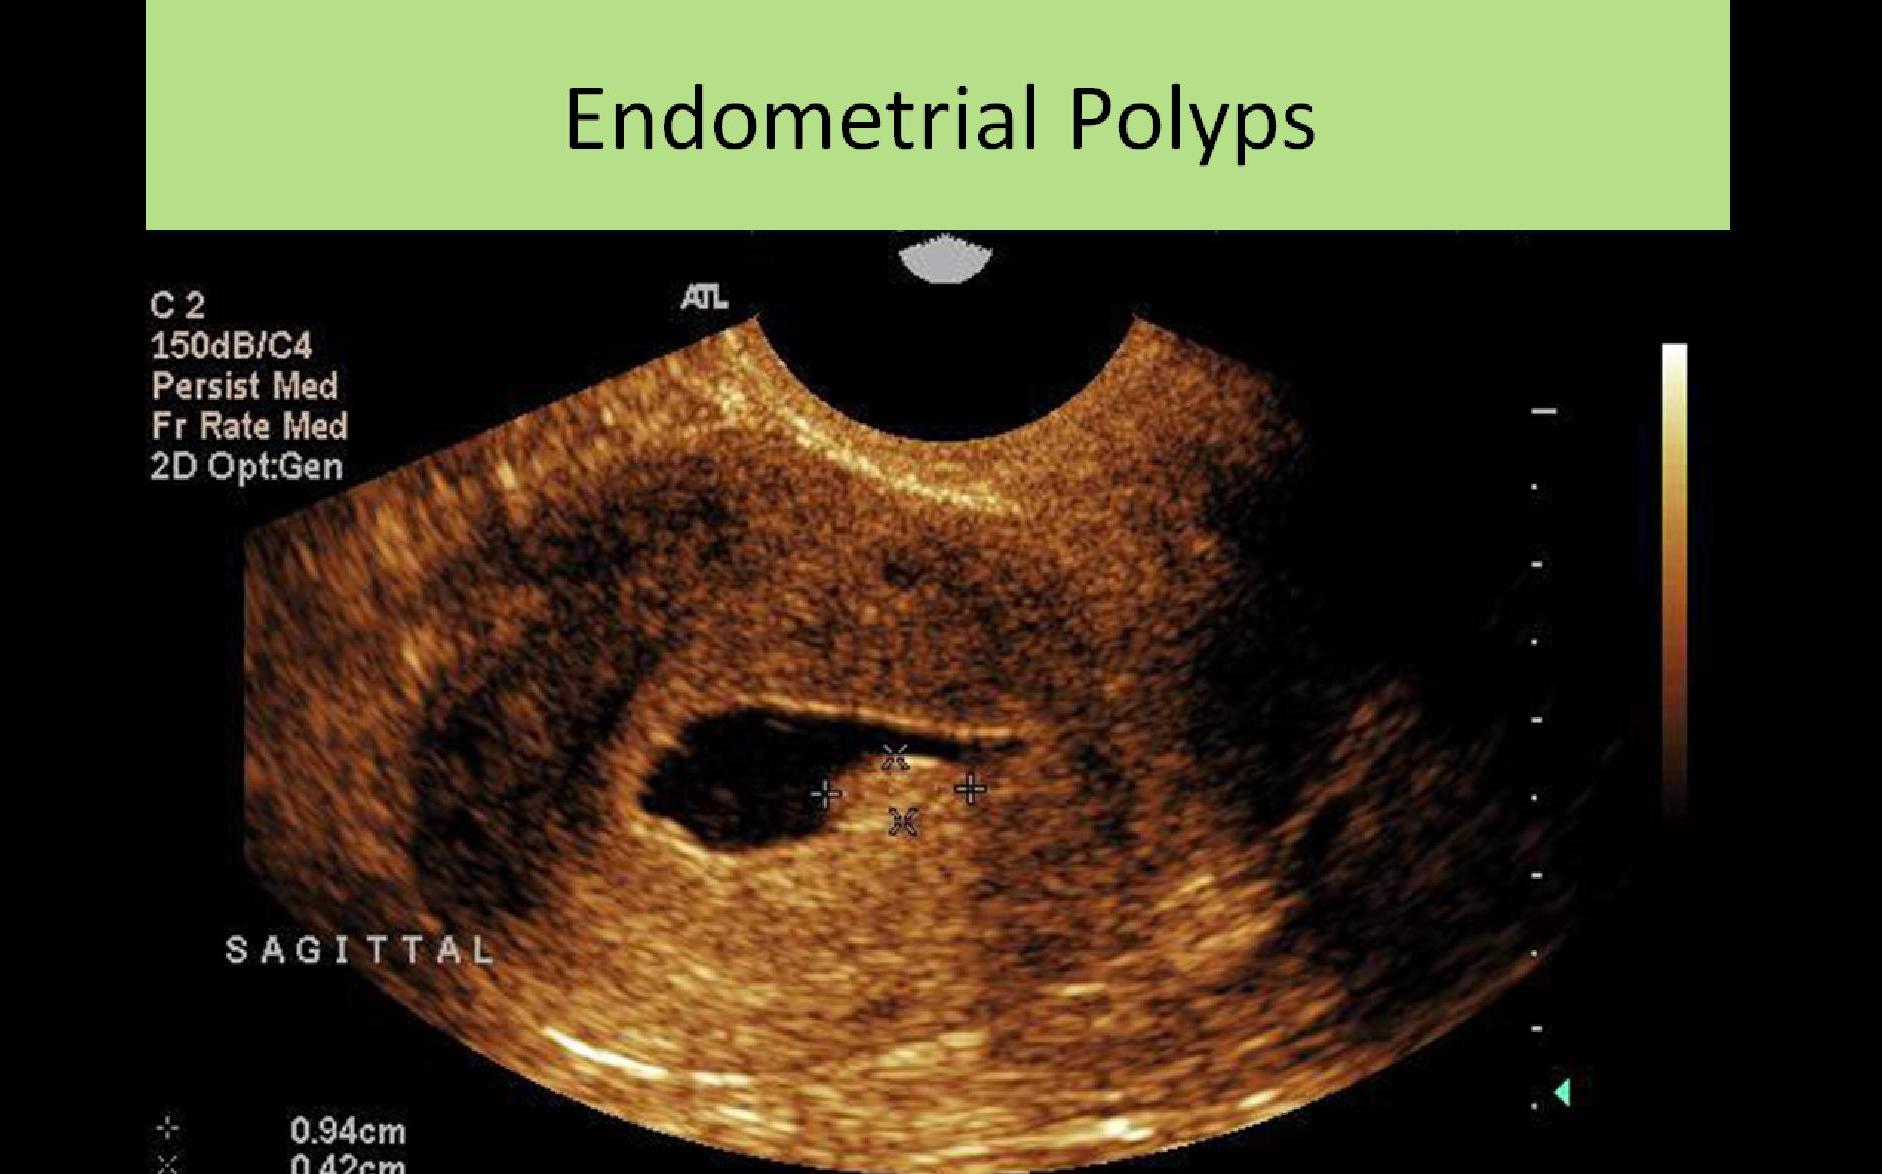

GYN Sonography: Anatomy, Physiology, Abnormalities and General Sonographic Information